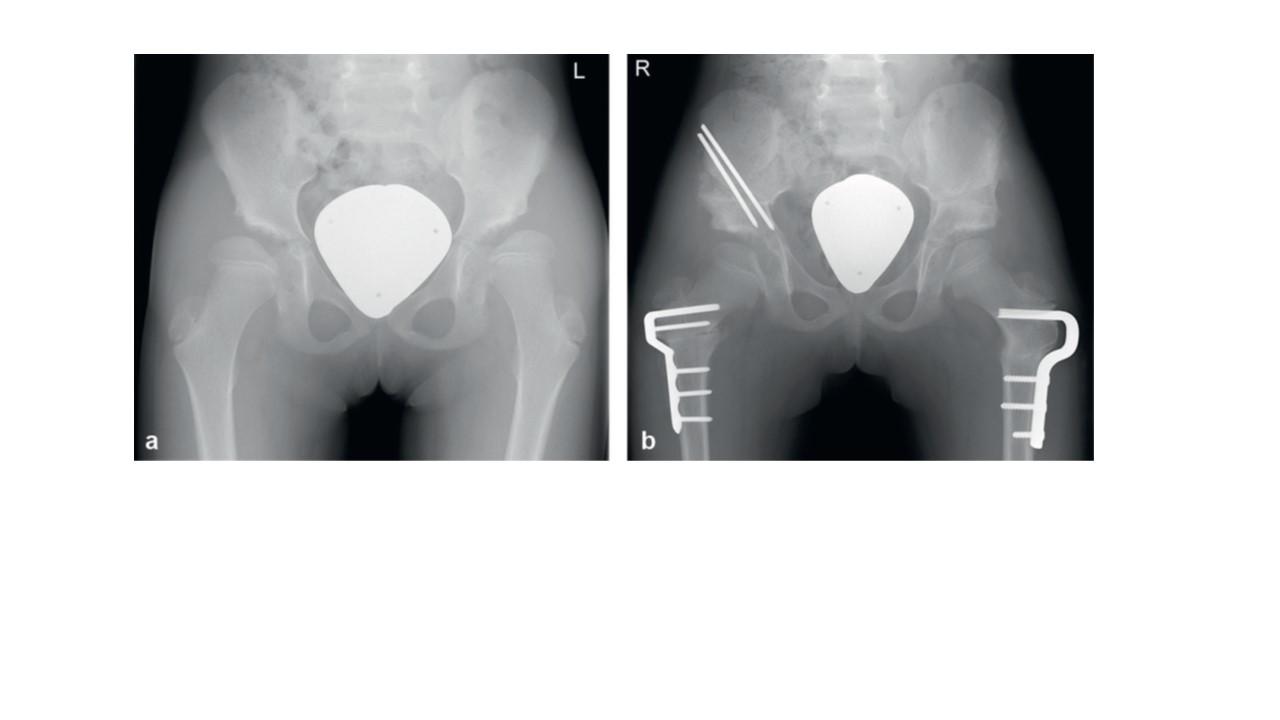

Bei Kleinkindern hat sich die sog. Beckenosteotomie nach Salter bewährt, bei der eine technisch relativ einfache Durchtrennung (=Osteotomie) des Darmbeins (=Ileum) und ein „Nachuntenklappen“ der Pfanne erfolgt. Die Korrektur wird mit sogenannten „Salter-Stäben“ gehalten. Diese Stäbe werden nach etwa 6 Wochen in einem kleinen ambulanten Eingriff wieder entfernt.

(a) zeigt einen 9-jährigen Patienten mit beidseitiger Minderüberdachung des Hüftkopfes und Steilstellung der Schenkelhälse. (b) zeigt den Zustand nach beidseitiger Beckenosteotomie nach Salter und Umstellungsosteotomie am proximalen Femur. Da der Eingriff in zwei Etappen erfolgte (zunächst auf der linken Patientenseite und dann rechts) sind rechts noch Salter-Stäbe einliegend. Zum Vergrößern auf das Bild klicken.

-